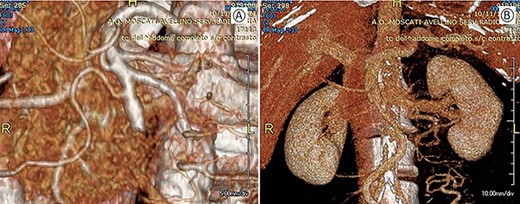

The postoperative course was uneventful. No bowel suffering or ischemia was highlighted by the abdominal CT-scan on seventh post-operative day (Fig. 4). The patient was discharged on eight post-operative day.

Postoperative CT with 3D vascular reconstruction; (A) arterial phase: superior mesenteric artery with its branches saved. (B) Venous phase: mesenteric-portal axis pervious.